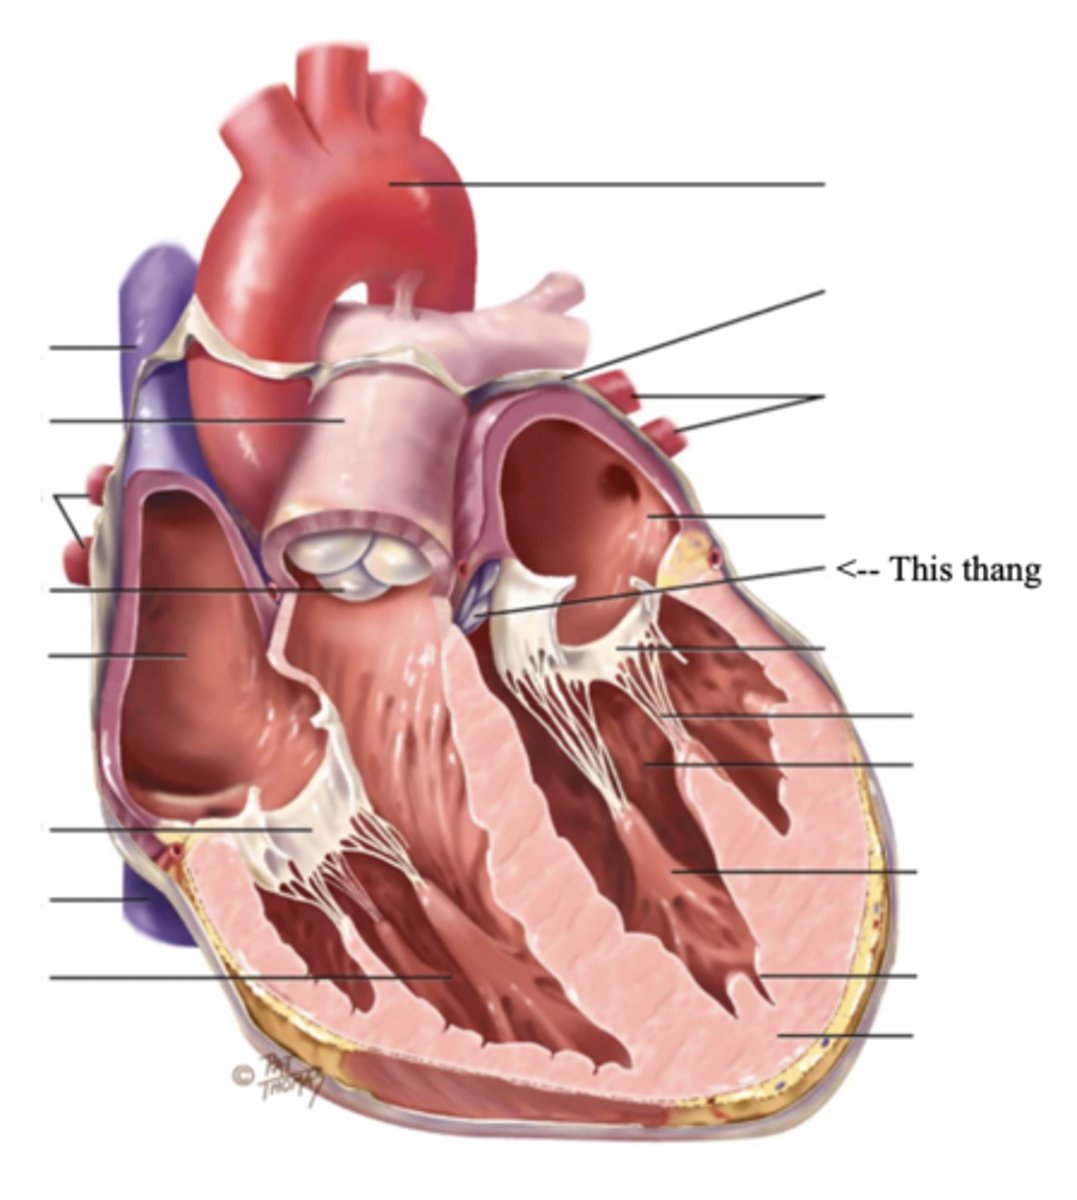

Anatomy of the Heart

2 Types of Chambers in the Heart

- Atrium

- Ventricles

Atrium (2)

A thin-walled reservoir for holding blood, located at the upper chamber of the heart

Ventricle (2)

The thick walled muscular pumping chamber of the heart located at the bottom chamber of the heart

2 Main Types of Valves of the Heart

- Atrioventicular

- Semilunar

Mitral (Bicuspid) Valve

- The left AV valve separating the left atrium from the left ventricle

- Connected by 2 chordae tendinae

Chordae Tendinae

Fibers (heart strings) attatched to the tricuspid and mitral valve which pull it closed when papillary muscles contract, preventing back flow of blood